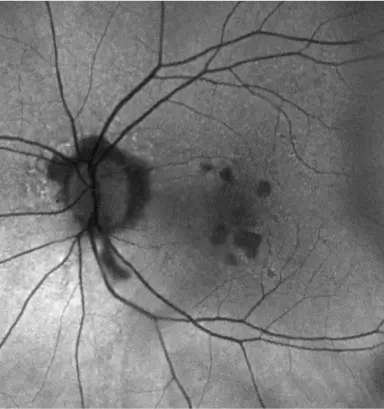

IZERVAY™ (avacincaptad pegol intravitreal solution) is indicated for the treatment of geographic atrophy (GA) secondary to age-related macular degeneration (AMD)